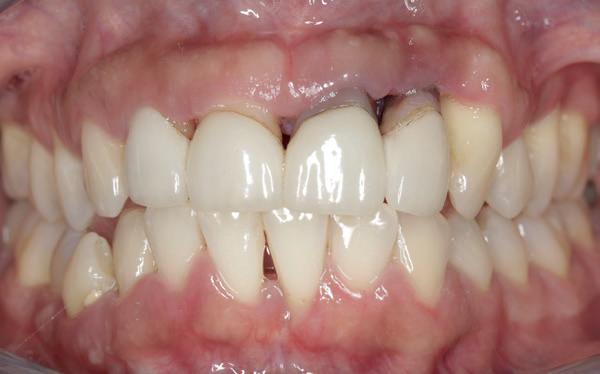

1. Studiofoto intake

aan zijn gebit gedaan behalve pappen en nathouden. Tandheelkundige zorg werd enkel verleend wanneer er zich een probleem voordeed (afbeelding 1, 3, 5).

Na afronding van de eerste twee behandelstappen werd parodontale stabiliteit bereikt, zoals waarneembaar op de parodontiumstatus en (röntgen)foto’s (afbeelding 6, 8). De patiënt toonde aantoonbare verbetering in mondhygiëne (afbeelding 4) en bleef gemotiveerd om de behandeling voort te zetten.